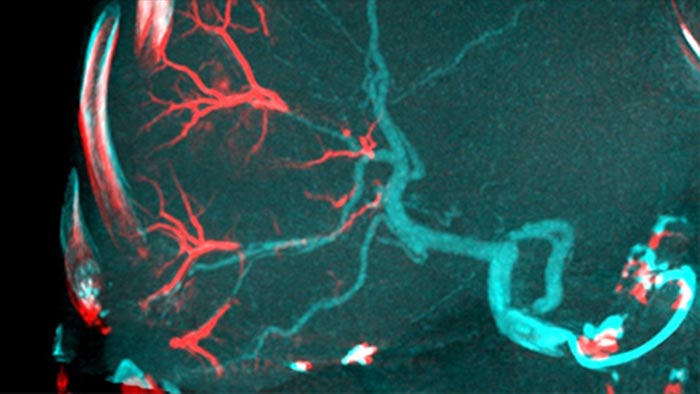

Detección automática del alimentador con EmboGuide

EmboGuide

Nuestra solución de Detección automática de alimentadores puede mejorar, de manera significativa, la detección de arterias nutricias en comparación con la TC de haz cónico sola.  EmboGuide le ayuda a maximizar la eficacia de sus procedimientos de QET, ya que potencialmente mejora su sensibilidad, reduce los falsos positivos y maximiza la concordancia entre lectores.1